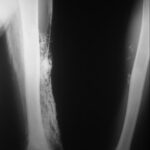

Dystrophic calcification frequently occurs in connective tissue diseases. Scleroderma and CREST syndrome (calcinosis cutis, Raynaud phenomenon, esophageal dysfunction, sclerodactyly, telangiectasia) are notable examples that are frequently associated with calcinosis cutis . In these disorders, nodules and plaques of calcium deposits may occur in the skin, subcutaneous tissue, muscle, or tendons. The calcium deposits most commonly occur on the upper extremities, especially on the fingers and wrists, but may occur in any area subject to trauma or motion. As the calcifications enlarge, they may ulcerate and exude a chalky material.

Dystrophic calcification also occurs in dermatomyositis . It is more commonly associated with juvenile rather than adult-onset dermatomyositis, occurring in 44 percent to 70 percent of children as opposed to 20 percent of adults. The calcification tends to occur 2 to 3 years after disease onset and most frequently appears on the elbows, knees, shoulders, and buttocks.18 The calcium deposits may be painful and can ulcerate. They also may exude a chalky material, form sinuses, and become chronically infected. Calcium salt deposition may become quite extensive, progressing along fascial planes of skin and muscle, forming an “exoskeleton,” and leading to significant morbidity and mortality. Calcinosis cutis in dermatomyositis is difficult to treat; however, if the patient survives long enough, the calcified nodules may improve spontaneously.

Pilomatricomas are the most common cutaneous neoplasms that manifest calcification and ossification. Approximately 75 percent of pilomatricomas show calcification and 15 percent to 20 percent show ossification. Ossification usually occurs within the connective tissue adjacent to the shadow cells, probably through metaplasia of fibroblasts into osteoblasts. Activating mutations in the adherens junction protein β-catenin have been identified in some pilomatricomas.46